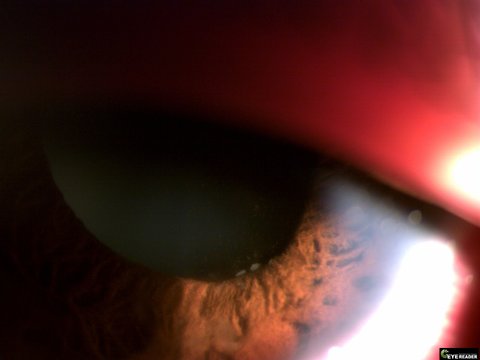

부디 코로나로 힘든 이시국에 몇달째 실명의 위기에서 고생하고있는 환자들(확인된 환자만 약 2백명 추정중)의 상황을 알릴수있게 도와주셨으면 좋겠습니다. 하단에는 참고를 위해 진균이 보이는 안구 사진과 함께 mbc뉴스 방영기사와 안내염 환자 카페 주소 및 국민청원주소를 첨부드리오니 많은 동의부탁드립니다.